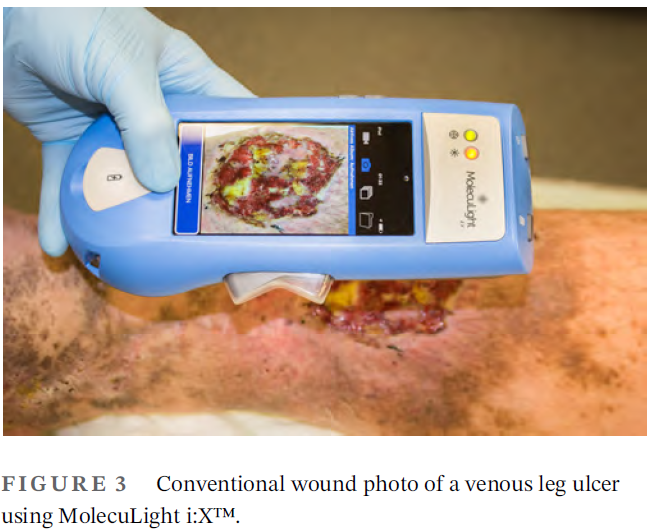

Prospective clinical study on the efficacy of bacterial removal with mechanical debridement in and around chronic leg ulcers assessed with fluorescence imaging

Moelleken, M et al. Int Wound J 2020